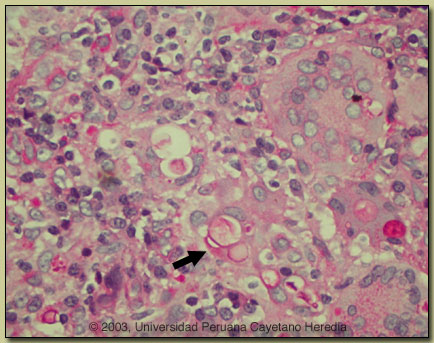

| Diagnosis: Paracoccidioidomycosis due to infection with Paracoccidioides brasiliensis. |

Discussion: The diagnosis was made by simple KOH preparation of a syringe aspirate of a cervical lymph node, which showed typical pilot-wheel shaped organisms consisting of spherical cells 10-40 microns in diameter with a thick birefrigent cell wall surrounded by several peripheral buds. A repeat lymph node biopsy showed granulomas with giant cells, and PAS staining [see image at right] showed characteristic large budding yeast forms of Paracoccidioides brasiliensis. The arrow points to a multiply budding yeast form within a giant cell stained red with PAS. Some singly budding forms can be seen in P. brasiliensis infected tissue. Hyphal forms are not seen in tissue in paracoccidioidomycosis. Culture is pending. A scraping of a forehead lesion was also positive by direct KOH examination. Direct scrapings or aspirates will be positive in the vast majority of cases of paracoccidioidomycosis with mucosal or cutaneous lesions.